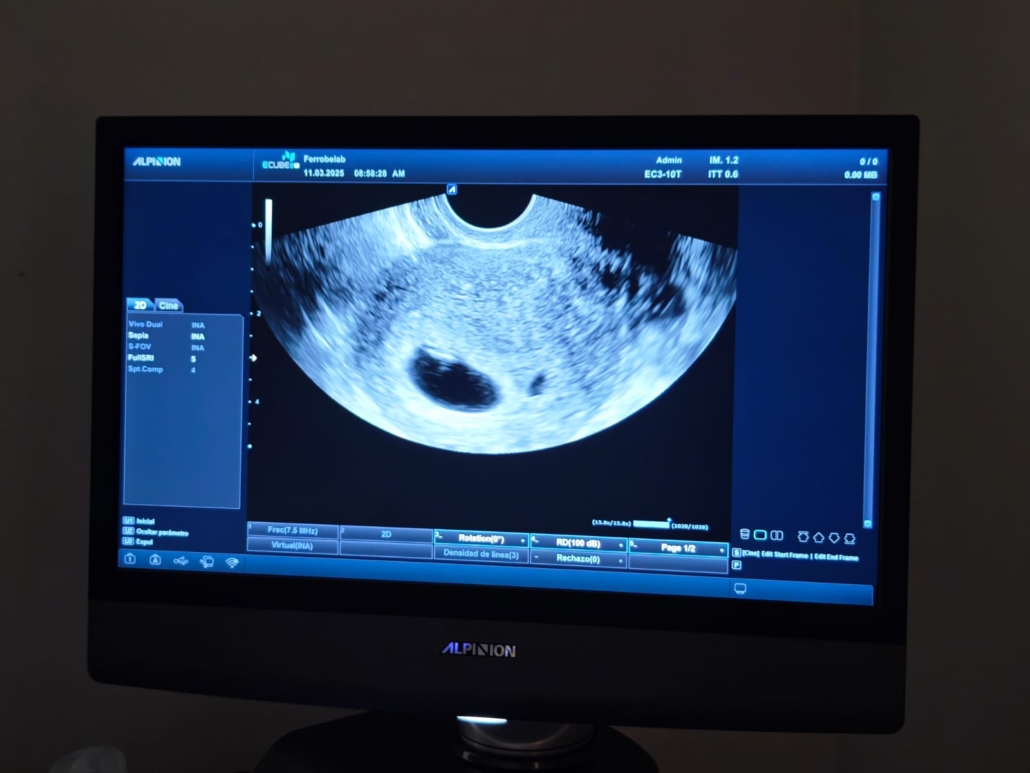

Hoy, en el quinto aniversario de su fallecimiento, le comunico a mi padre, que está en los Cielos, que va a ser bisabuelo –si Dios quiere– en unos meses.

Besos, padre. Te adjunto la primera foto. Pide por la criatura y por el mundo en el que habrá de nacer. Tú que estás con el Padre. Hágase Su voluntad.